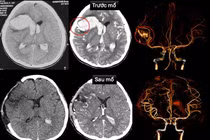

Chấn thương sọ não ở người cao tuổi, tưởng nhẹ, hậu quả có thể tử vong

Ở người cao tuổi, một cú ngã tưởng chừng nhẹ cũng có thể gây tụ máu não tiến triển nhanh, các triệu chứng không rầm rộ, nhưng xấu đi rất nhanh.